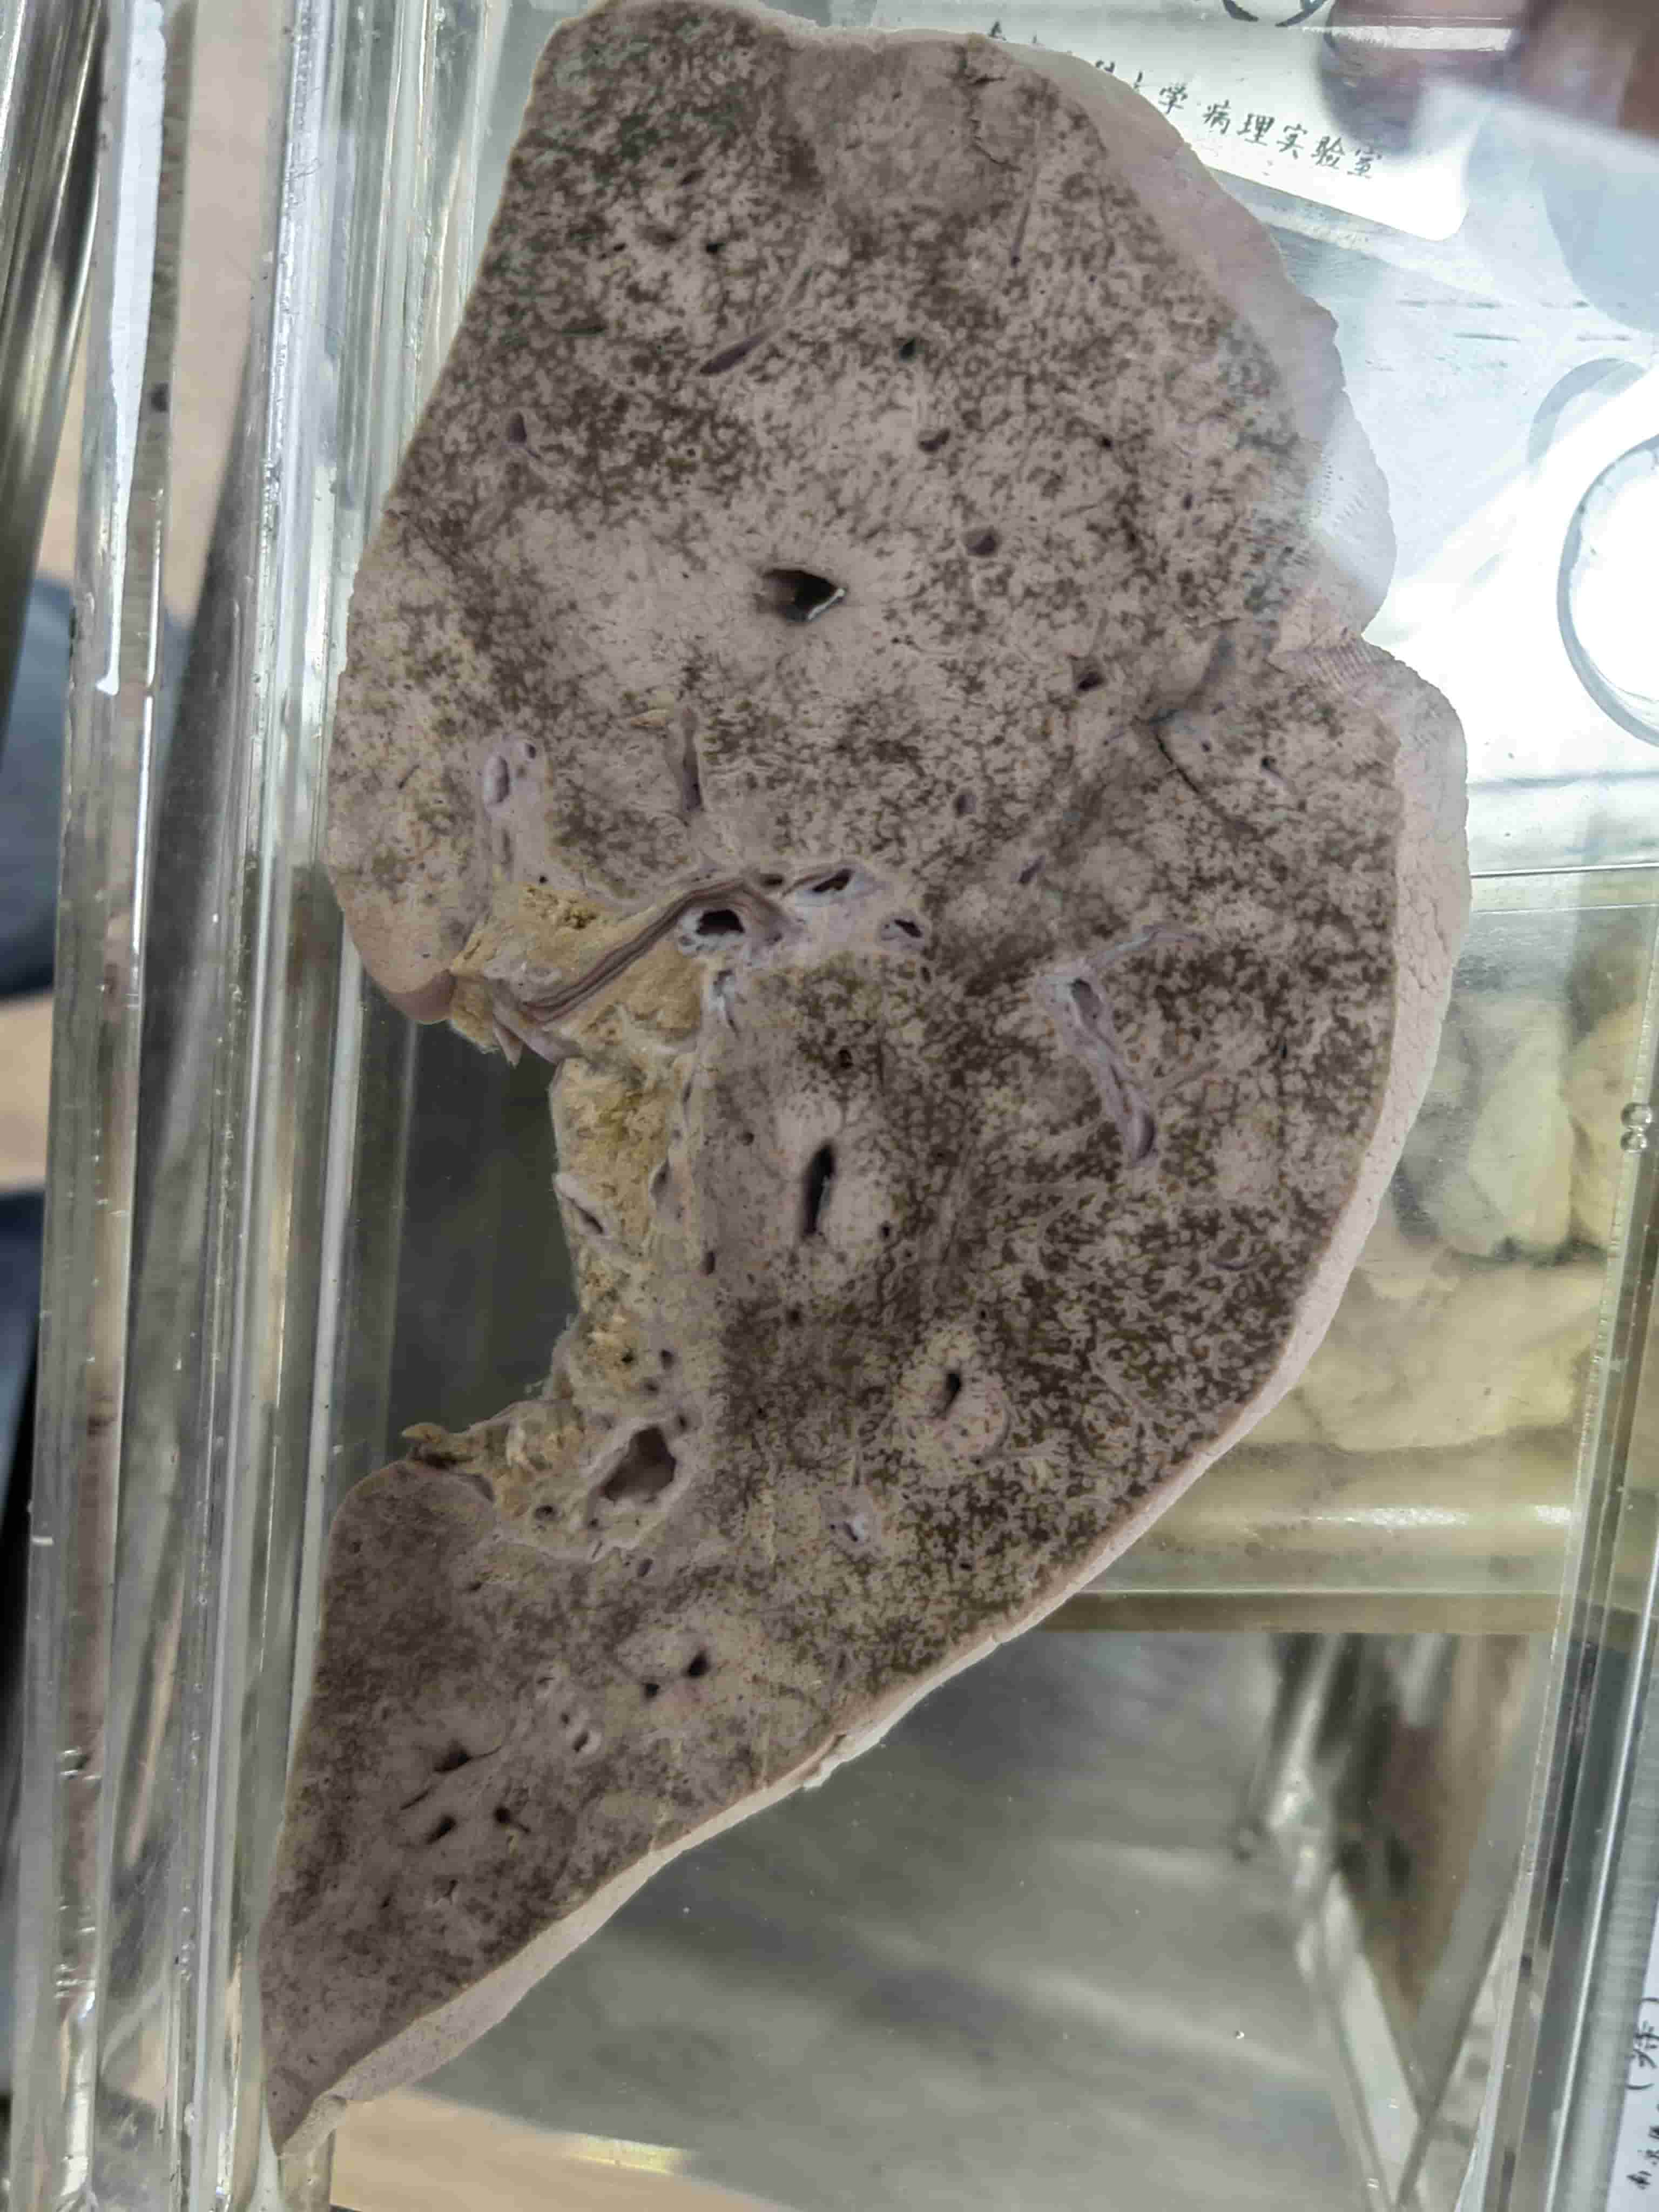

肾萎缩

- 肾盂积水、肾实质压迫性萎缩

- 皮质、髓质萎缩变薄

![image]()